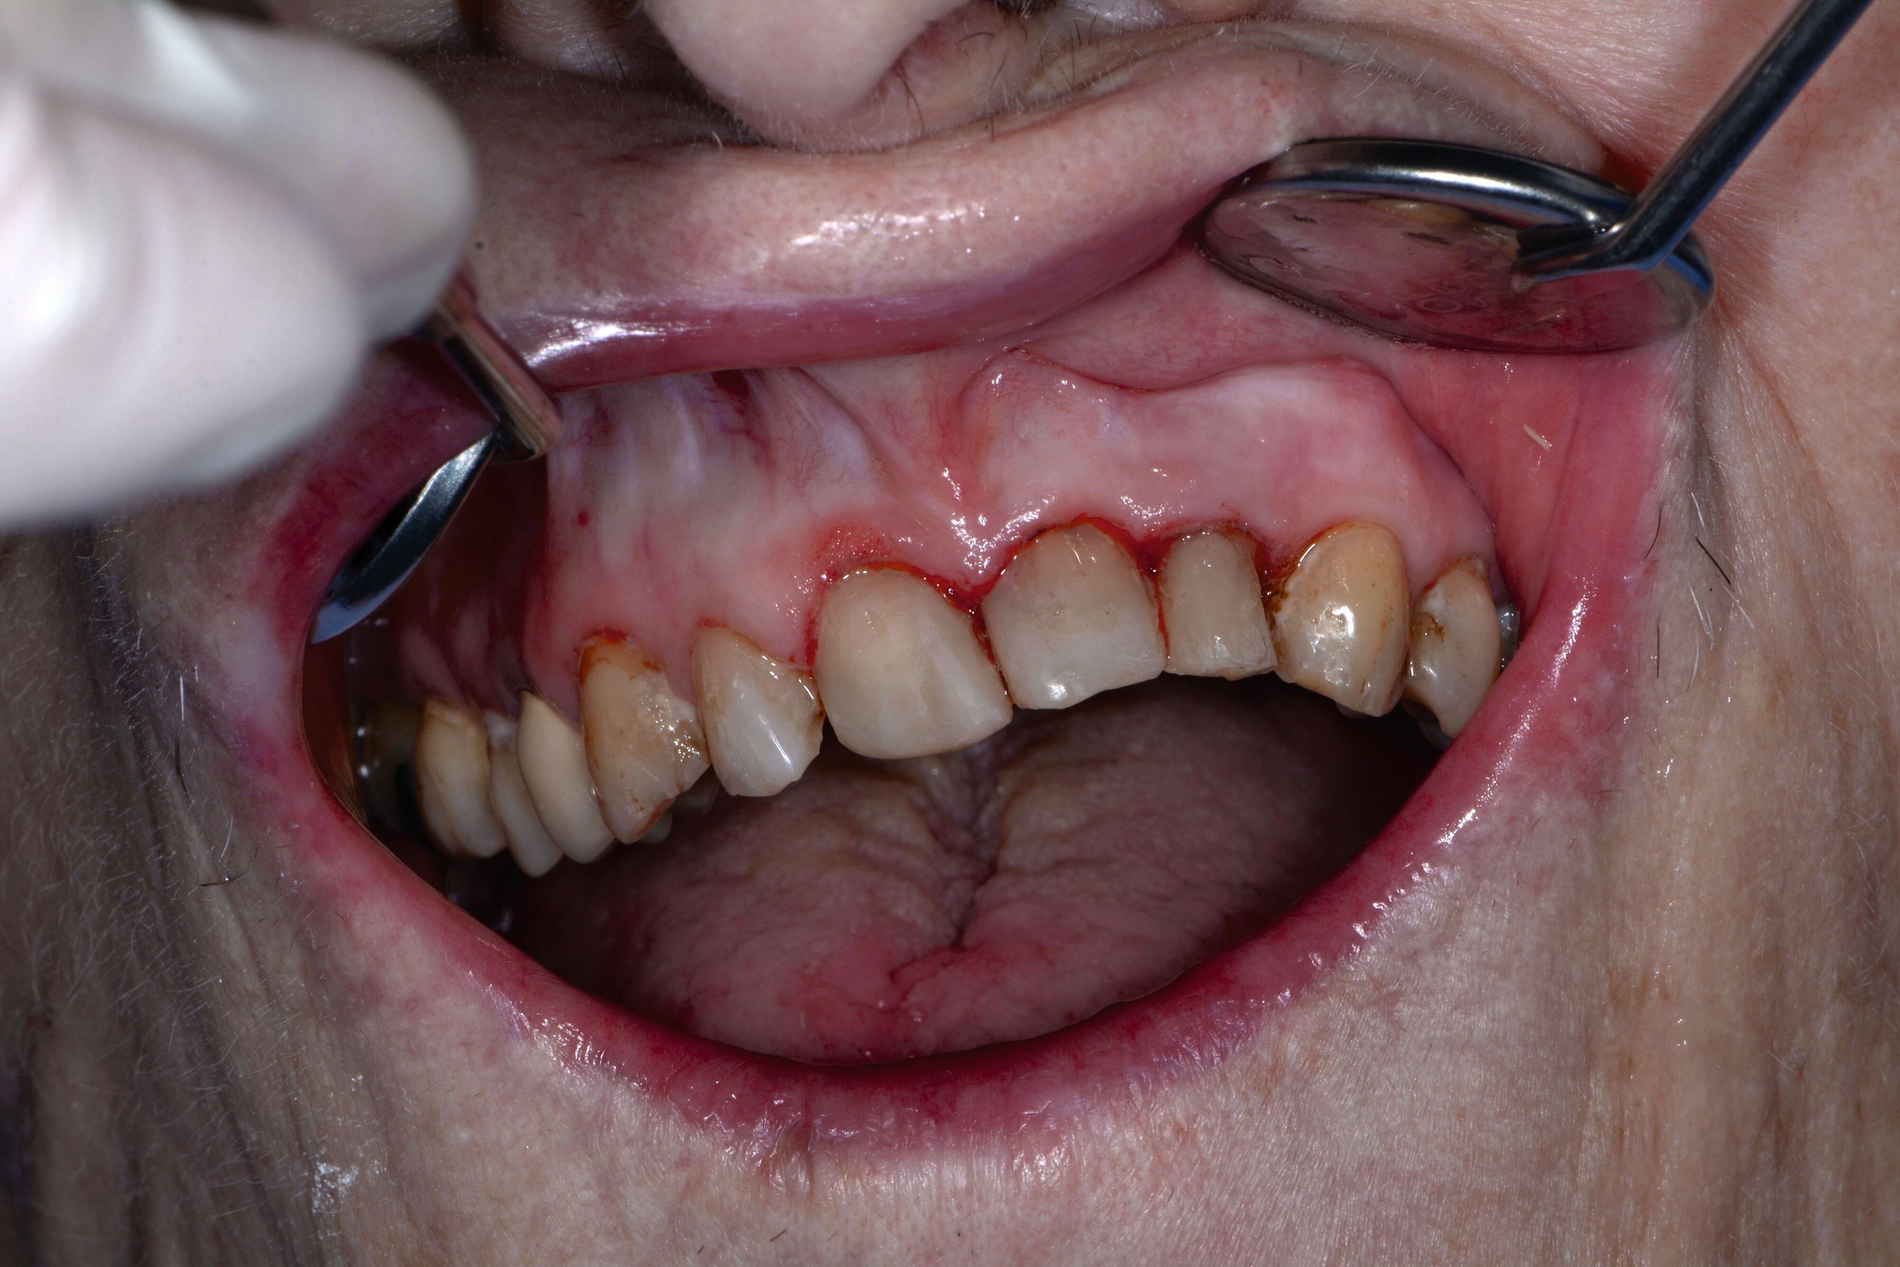

Die Herausforderungen der zahnmedizinischen Betreuung im höheren Lebensalter liegen außerhalb der Mundhöhle und haben nur indirekt etwas mit dem Alter zu tun. Im höheren Lebensalter steigt die Gefahr für Erkrankungen und Funktionseinschränkungen wie Gebrechlichkeit (Frailty), Demenz und Depressionen und/oder internistische sowie muskuloskelettale Erkrankungen. Diese Erkrankungen und Funktionseinschränkungen führen zu einer reduzierten Mundhygienefähigkeit der betroffenen Person. In der Folge kommt es besonders im vorgeschädigten Gebiss zu einer schnellen Progression kariöser oder parodontaler Erkrankungen. In Kombination mit organischen Funktionseinschränkungen wie zum Beispiel einer medikamenteninduzierten Xerostomie führt die Summation der Noxen – auch bei Personen, die ihre Mundgesundheit bis dato aufrechterhalten haben – zu oralen Komplikationen wie Zahnverlust und Entzündungen (Abbildung 1).